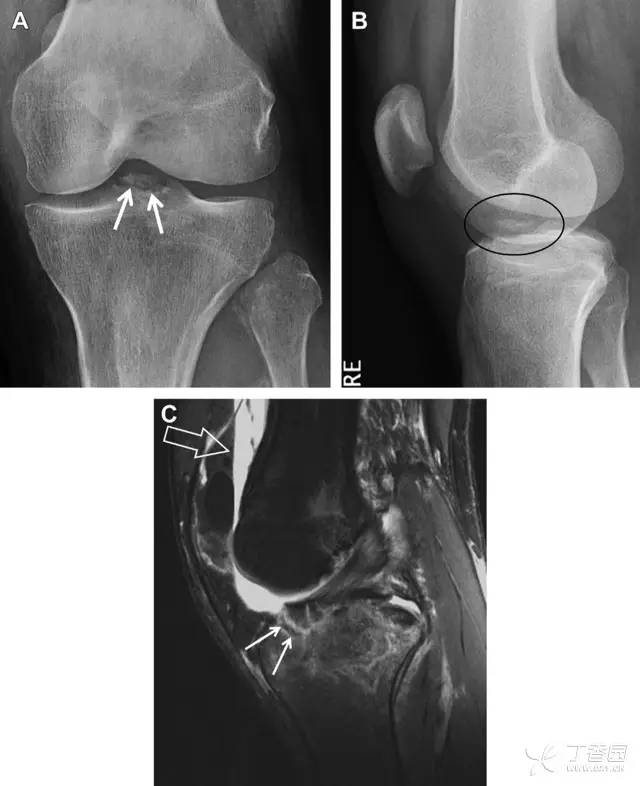

膝关节撕脱骨折和压缩骨折常伴发于韧带损伤,若想准确诊断,在了解这些骨折高发部位的同时,还需仔细认真地阅片,否则有些骨折就被漏诊了。

前交叉韧带撕脱骨折常发生在胫骨髁间嵴(图 1)。这种骨折在青少年中常见,但在成年人中也并不像大家想象的那么少见。

图 1 摩托车事故患者前交叉韧带撕脱性骨折

A 正位片示胫骨髁间嵴底部骨折(箭头),关注别把这个骨折碎片错认为关节内结构。B 侧位片示胫骨上方可见一细长型骨折碎片(椭圆)。C MRI 矢状位 T2 加权像示前交叉韧带附着于撕脱的骨折碎片上(箭头),关注周围存在骨髓水肿和积脂血征(空箭头)。

图 2 扭伤后的股骨外侧髁凹陷征

A 侧位片示股骨外侧髁凹陷。B MRI 矢状位 T2 加权像示股骨外侧髁及胫骨后外侧骨挫伤(空箭头)。胫骨近端随着后交叉韧带撕裂发生移位,露出外侧半月板的后角(弧形箭头)。